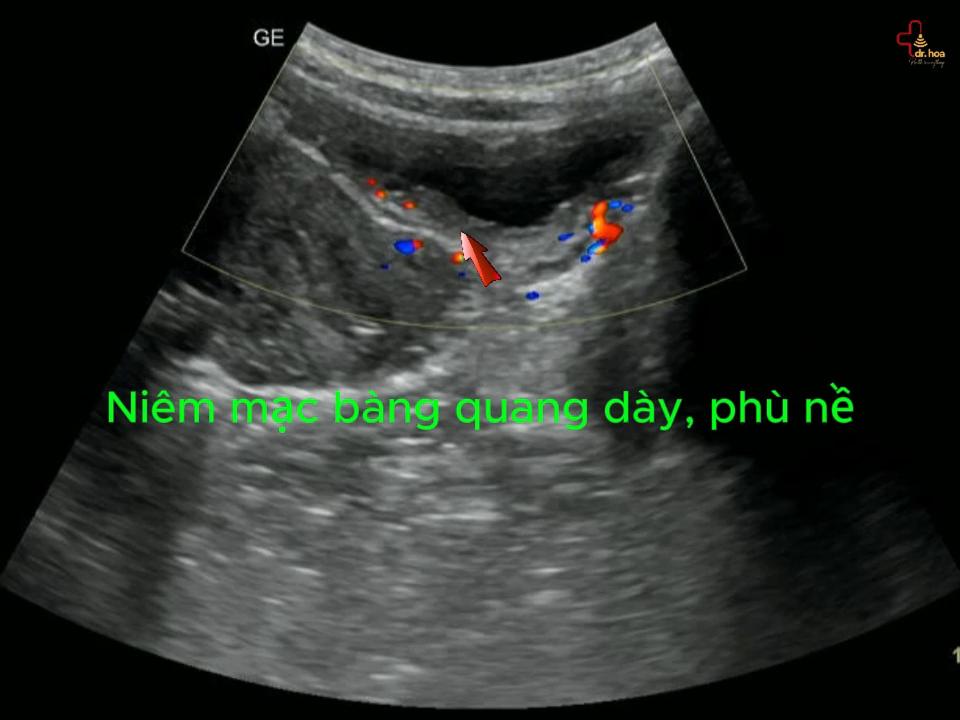

- Hệ thống siêu âm Doppler: dùng trong những trường hợp chuyên sâu.